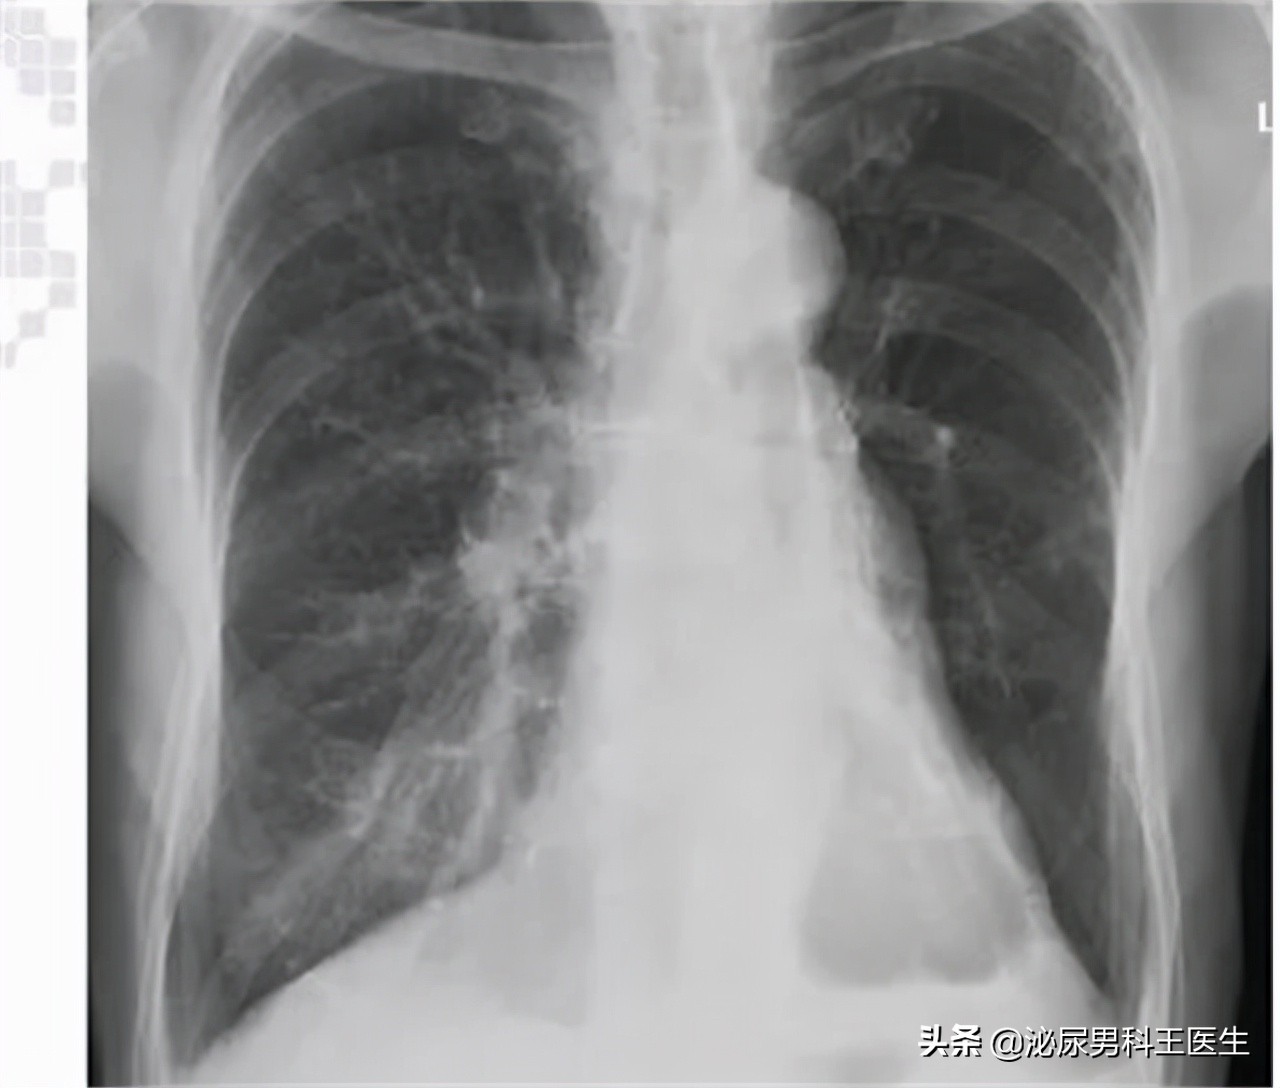

以下截取老陈的部分病例报告单:

【检查结果】:体循环有淤血,两肺底湿啰音,室性奔马律和交替脉。左心室射血分数较高,肺部室壁较厚

【诊断结果】:肺部高血压合并慢性心力衰竭